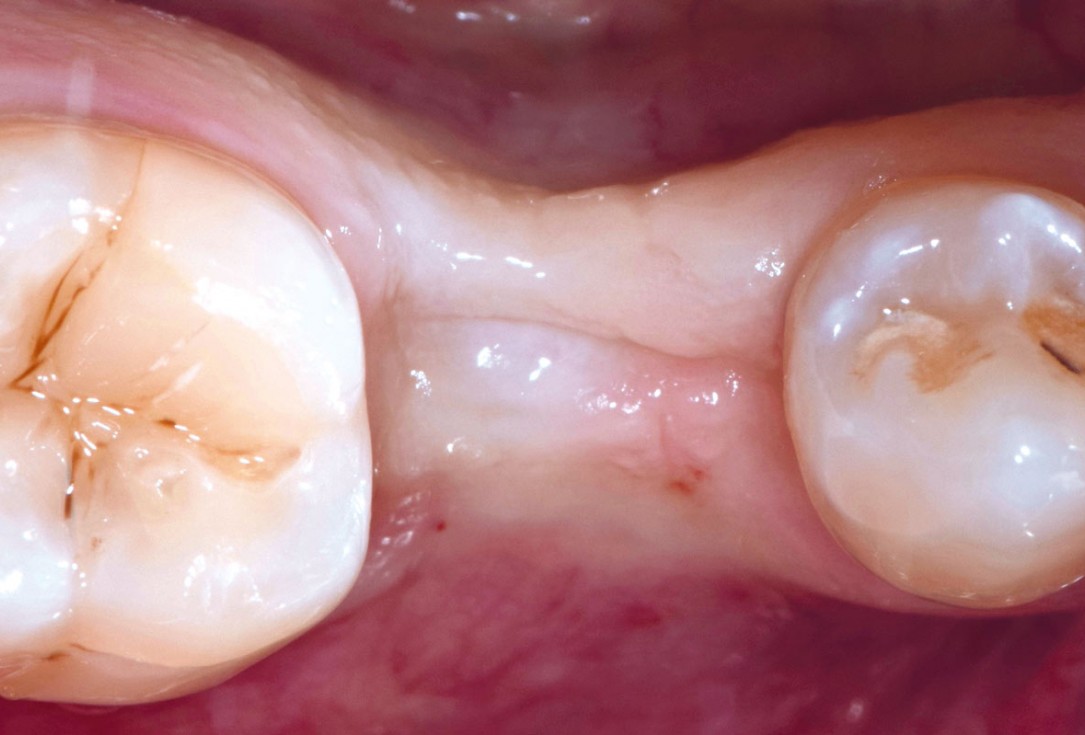

1/17 - Initial clinical situation showing tooth 45 not worth preservingApplication of mucoderm® for soft tissue management around single implants at second stage surgery Dr. C. De Annuntiis

5/17 - Healing of the extraction socket at 3 monthsApplication of mucoderm® for soft tissue management around single implants at second stage surgery Dr. C. De Annuntiis